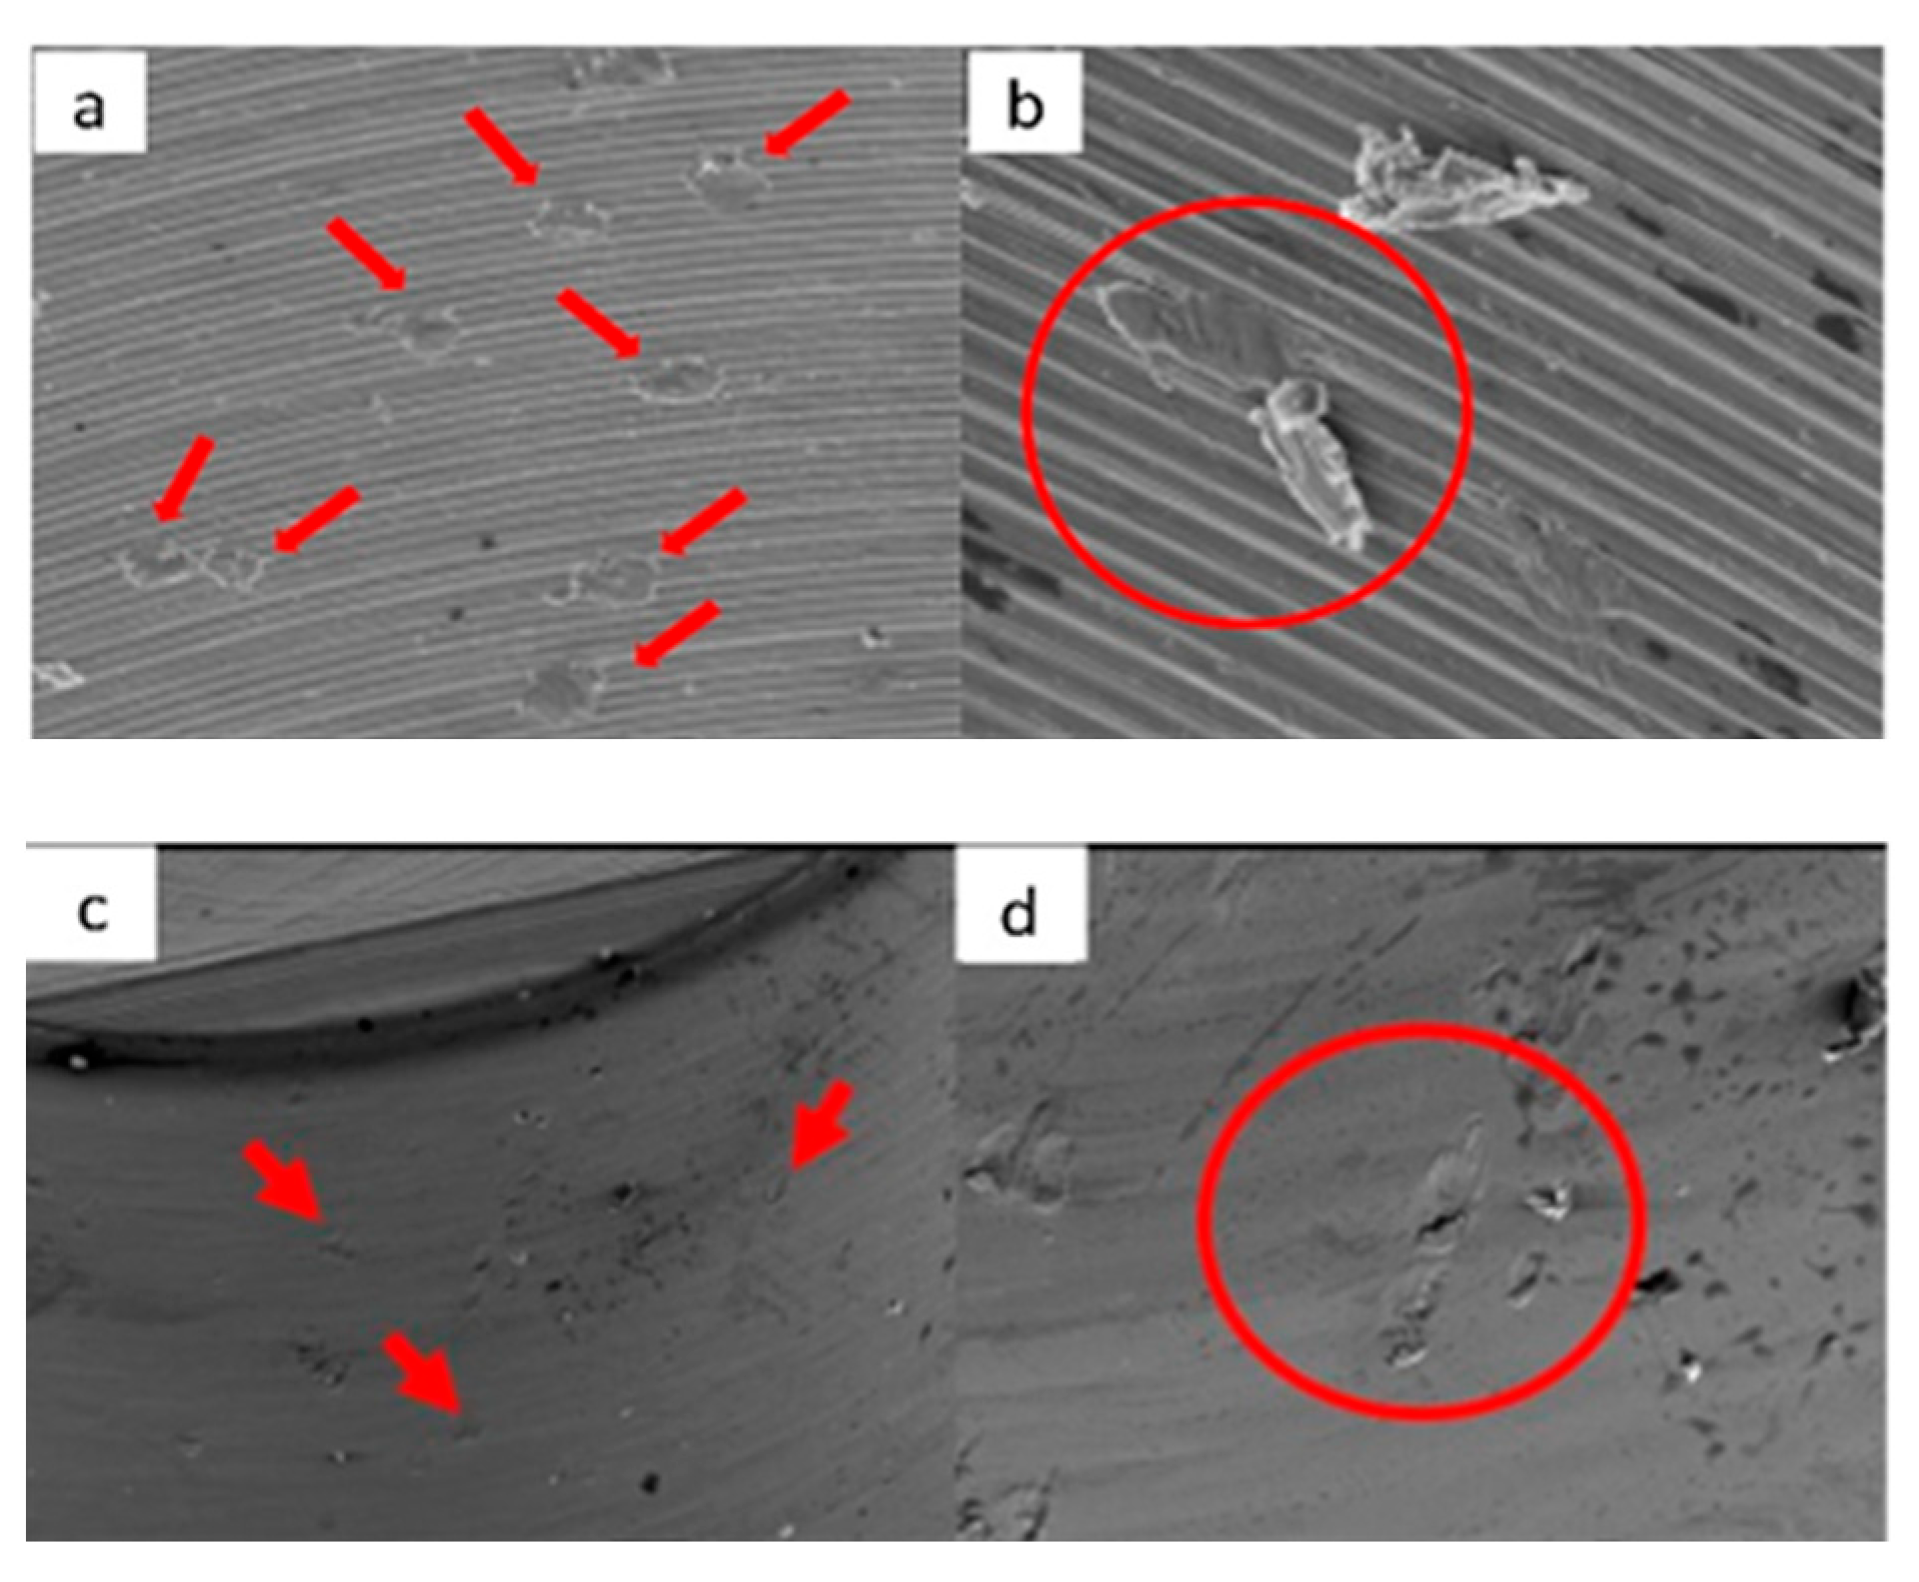

3.1. SEM

3.1.1. KL Implants

3.1.2. Essential Implants

3.1.3. SK2 Implants

3.1.4. Vega Implants

4.1. SEM Evaluation